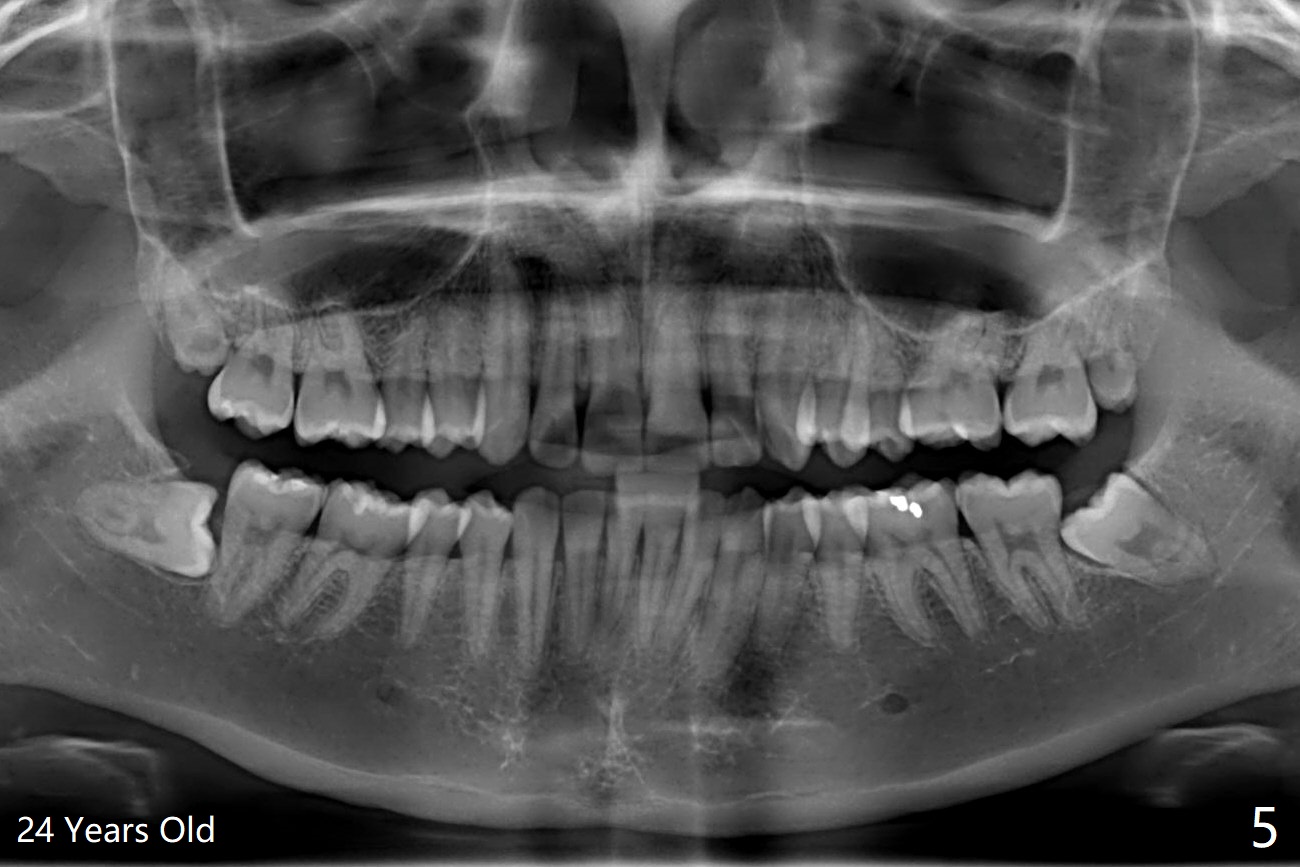

A 25-year-old woman, under our care for the last 11 years (Fig.1-6), returns for #1 and 32 extraction (1 year after #16 and 17 extraction (Osteogen plug)). Preop PA shows that a portion of the lower impacted tooth may be located buccal to the tooth #31 (Fig.4 black dashed line). An accessory incision is moved from distobuccal to midbuccal (Fig.7 arrowheads) to reduce postop loss of bone graft (Fig.8 B) from the incision. In fact the incision should be further moved to mesiobuccal (Fig.9 red line) if buccal impaction is suspected (curved black line). The buccal impaction of #32 of her father is more severe.